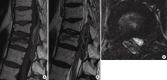

Spinal epidural hematoma (SEH) is a rare cause of nerve root or cord compression; its pathogenesis is not always clearly recognizable. The aim of this paper was to investigate possible etiopathological factors in a consecutive series of patients affected by traumatic SEH treated at our institution. Seven patients with neurologic impairment due to traumatic SEH were retrospectively analyzed after diagnosis and surgical treatment. Thoracic localization was found in 5 cases, and lumbar and cervical localization were found in 1 patient each. One patient was affected by ankylosing spondylitis and one by diffuse idiopathic skeletal hyperostosis. SEH was associated with spine fractures in 6 cases. Only 2 cases of traumatic SEH resulted from high-energy trauma. All patients underwent surgical decompression within 24 hours after admittance to the hospital. Three patients recovered completely, 3 remained paraplegic, and 1 remained monoplegic. Several concomitant conditions are suggested to be predisposing factors for the development of SEH, although its inherent mechanism is still unknown. Two patients in the present series were affected by rheumatologic disorders, confirming the elevated incidence of hematomas in such patients compared to the normal population. Three very unusual cases of SEH occurred in senile patients affected by osteoporotic fractures. Early diagnosis and urgent decompression of the hematoma remain mandatory.